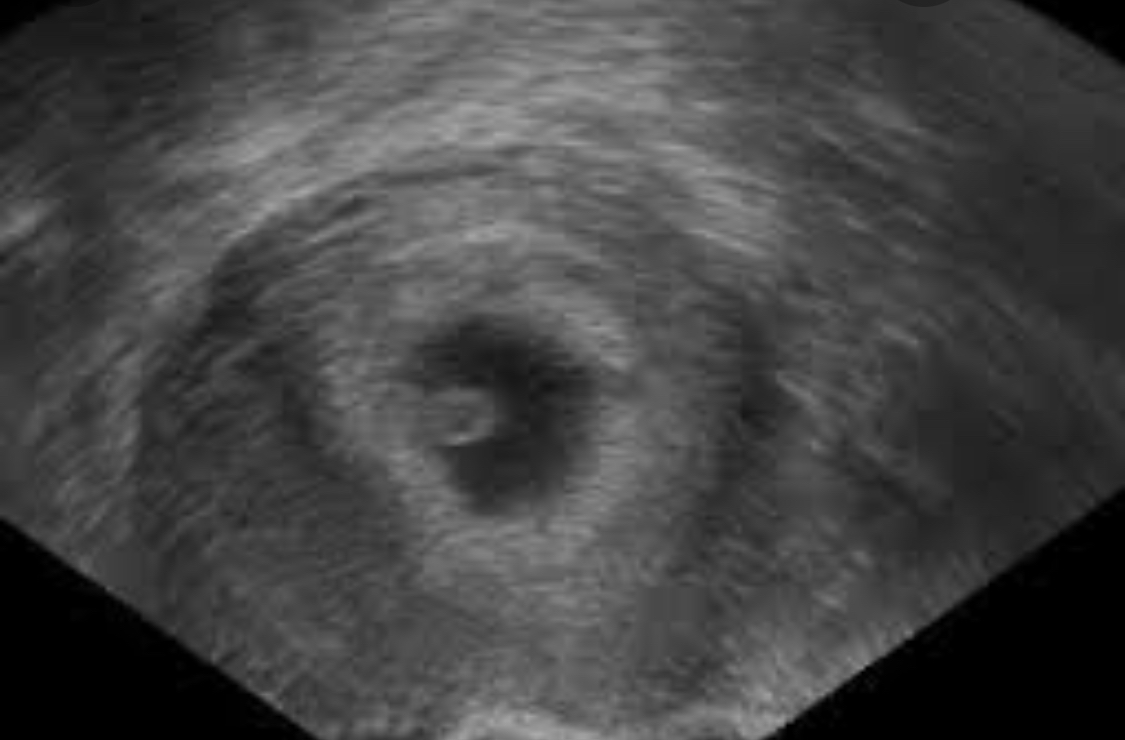

Pro představu přidávám ultrazvuk z internetu, vypadalo to zhruba takhle.. Svoji fotku bohužel nemám.